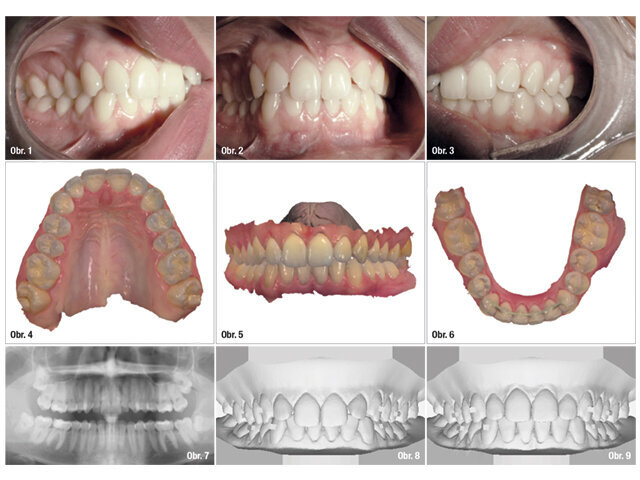

Pacientka měla na pravé i levé straně okluzi I. třídy. Zuby 11 a 21 byly skloněny palatinálně a zuby 12 a 22 vestibulárně. V dolní čelisti byl mírně rotovaný zub 31 (obr. 1–7).

Případ byl prostudován pomocí softwaru 3Shape OrthoAnalyzer. Ten nám umožnil vytvořit si ortodontický wax-up a plán léčby pro konečný výsledek (obr. 8–10). Měli jsme možnost předem vidět postup terapie na krátkém videu.